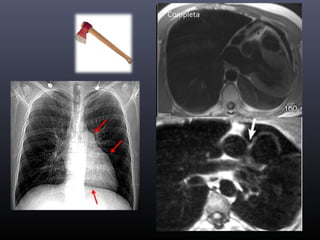

Ausencia congénita de pericardio

ParcialCompleta

Taponamiento pericárdico

• Signos radiológicos:

Derrame pericárdico

Colapso pared del VD (signo del corazón

aplanado)

Balanceo cardiaco

Movimiento paradójico del septo

interventricular

Dilatación de venas cavas

Compresión del seno coronario

Reflujo de contraste a vena ácigos

No depende exclusivamente del volumen  Presión intrapericárdica >20mmHg